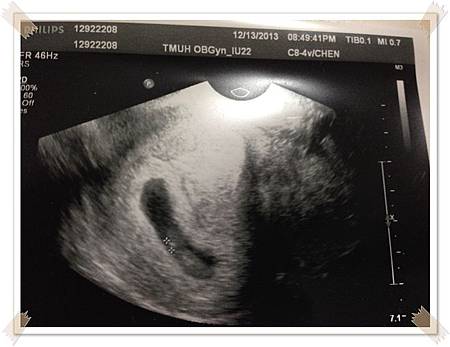

玩回來剛好5週去照囊胚,,看到胚胎著床在子宮裡,心裡滿是喜悅,

懷孕5W的超音波照片忘了跟護士要

通常大醫院都得自己要才會給,如果沒要就不會給了,

一般婦產科診所則是會自動印一堆給你